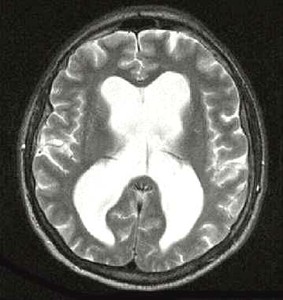

Головний мозок має внутрішні і зовнішні порожнини, заповнені цереброспинальной рідиною (ліквором). Причина головного болю при підвищенні внутрішньочерепного тиску - надлишкове скупчення рідини в цих порожнинах. Детальніше про це тут .

Речовина мозку на знімках позначено сірим кольором, а рідина - білим. Зліва - нормальна ширина рідинних порожнин (шлуночків) мозку

Праворуч - шлуночки переповнені рідиною, внутрішньочерепний тиск підвищений, є головний біль

Симптоми. Монотонна головний біль, що розпирає або давить, що розповсюджується на всю голову, відчуття «важкої» голови, біль в області очей, нудота. Можлива блювота, що не приносить полегшення. Нерідко виникає відразу після пробудження. Може посилюватися від яскравого світла і гучних звуків. Провокується зміною погоди, вживанням великої кількості солі і рідини, алкоголем, втомою, форсованої фізичним навантаженням, вечірнім переїданням.

Небезпеки.Тривало підвищений внутрішньочерепний тиск призводить до погіршення в роботі головного мозку. В першу чергу страждає вегетативна нервова система. Звідси судинна дистонія , Стомлюваність. Можливі й інші розлади - зниження слуху і шум у вухах , Зниження зору, зниження пам'яті та уваги, сексуальні розлади, депресія, порушення сну. Лікування і прогноз. Деяким пацієнтам доводиться періодично повторювати лікування. Детальніше тут